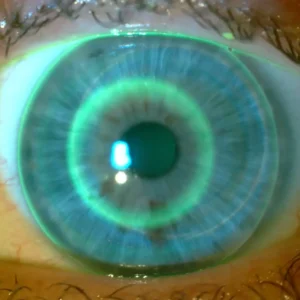

- Jak ocenić dopasowanie soczewek ortokorekcyjnych

- Jak analizować mapy rogówki pod kątem soczewek ortokorekcyjnych?